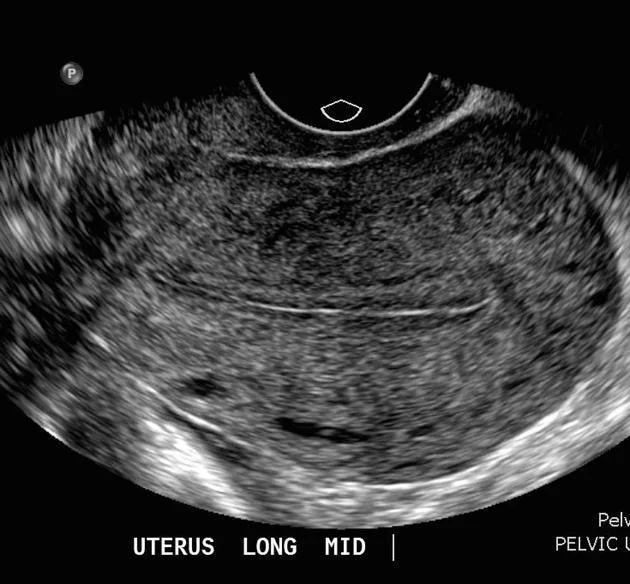

- US: empty uterus.

| Complete miscarriage | Empty uterus Serum h CG to exclude EP (If no previous one with intrauterine pregnancy ) | Vaginal bleeding & Abdominal pain resolved Speculum cx os closed | Supportive |